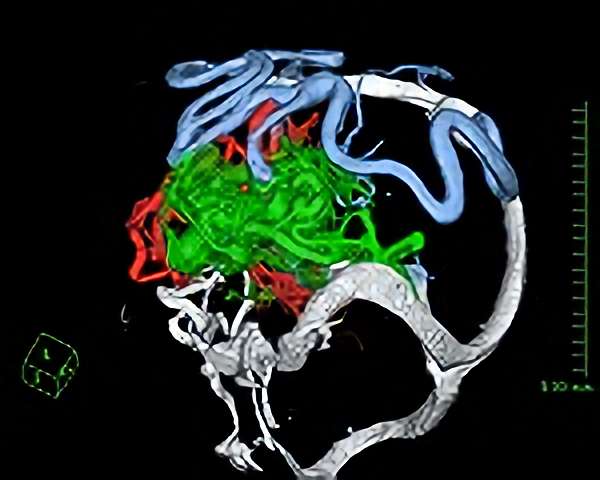

脳血管撮影

手術前

手術後

手術中